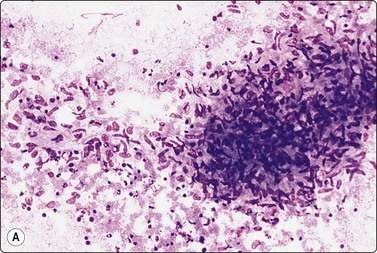

Fig. 5.14 Toxoplasmosis

(A) Granuloma-like cluster of histiocytes with epithelioid features; (B) Activated lymphoid cells possibly including some monocytoid B-cell forms. (MGG, HP).

image image

The reactive pattern is variable depending on the degree of stimulation, the number and size of germinal centers and on whether the sample derives mainly from a germinal center or from interfollicular or paracortical tissue. Germinal center material is represented by poorly defined tissue fragments composed of centroblasts, centrocytes, ‘tingible body’ macrophages (Figs 5.4, 5.5), and a number of lymphocytes which adhere to the syncytial cytoplasm (pale gray/violet in MGG) of dendritic reticulum cells (Fig. 5.6A). Dendritic reticulum cells have oval or round nuclei with a smooth nuclear membrane, a coarsely granular, uniformly distributed chromatin and small distinct nucleoli (Fig. 5.6B). The cytoplasm is dispersed in the background. A smear, which derives mainly from interfollicular tissue, consists predominantly of lymphocytes with a variable but much smaller number of scattered immunoblasts, plasma cells, non-specific histiocytes and endothelial cells (Fig. 5.7). Multiple biopsies diminish the bias caused by selective sampling.

The main features which distinguish a reactive process from lymphoma are:

1 a mixed population of lymphoid cells representing the whole range of lymphocyte transformation from small lymphocytes to immunoblasts and plasma cells,

2 a predominance of small, sometimes slightly larger ‘stimulated’ lymphocytes, which have small round nuclei and a characteristic chromatin pattern of large, ill-defined condensations,

3 centroblasts and centrocytes associated with dendritic reticulum cells and tingible body macrophages derived from germinal centres.87,88